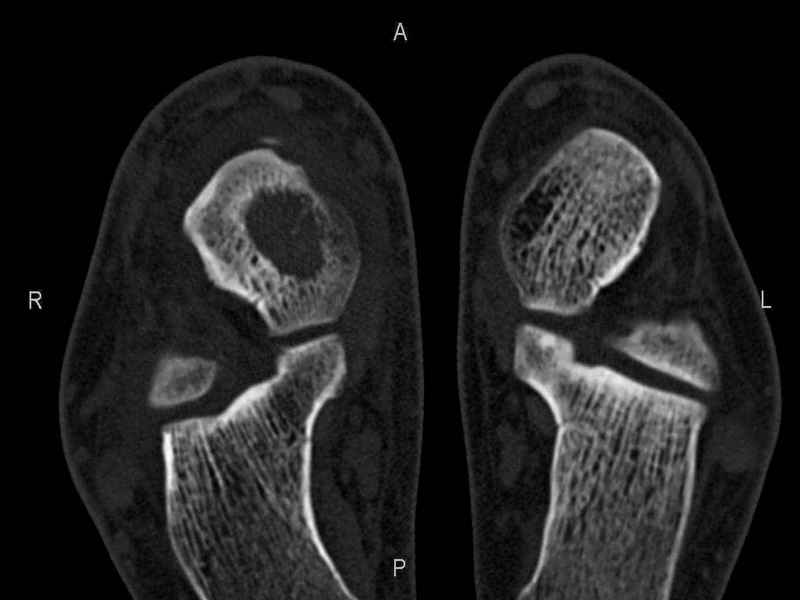

Уважаемые коллеги, обратился за помощью пациент, мужчина, 25 лет. С жалобами на болевой синдром в области голеностопного сустава и среднем отделе стопы. Травму отрицает. Со слов, болевой синдром в течении 1 года. Последние 1-1.5 мес периодически вынужден пользоваться костылями. После ограничения нагрузки боли уменьшаются.Соматически здоров. До появления болей активно занимался рукопашным боем. На СКТ картина рассекающего остеохондрита блока таранной кости, киста шейки таранной кости с признаками импрессии суставной поверхности. А также - разрастания переднего края б\берцовой кости сопровождающиеся клиникой импиджмент синдрома. Предполагаемый план лечения- удаление свободного фрагмента суставного хряща из трансмаллеолярного доступа с рассверливанием поверхности дефекта, кюретаж кисты шейки с заполнением полости биокомпозитом + дебридмент переднего отдела голеностопного сустава. Прошу высказать своё мнение, за и против, предполагаемого плана лечения. А также по возможности ответить на вопросы: 1. Есть ли необходимость в улучшении васкуляризации таранной кости (например подтаранный артродез). 2. Учитывая планируемое применение биокомпозитного цемента целесообразно ли заполнение им дефекта блока таранной кости с моделированием края суставной поверхности.